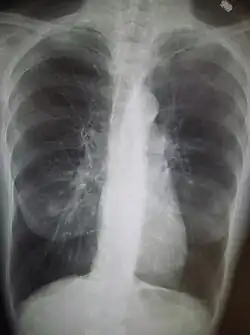

Une radiographie pulmonaire montrant une BPCO sévère ; on note la petite taille du cœur par rapport au thorax.